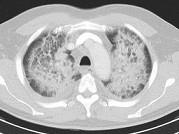

问题 男,51岁,呼吸困难,心悸,咳大量粉红色泡沫痰,结合CT,最可能的诊断是 ( )

选项 A.肺泡性肺水肿 B.间质性肺水肿 C.肺泡癌 D.肺泡蛋白沉积症 E.肺结核

答案 A